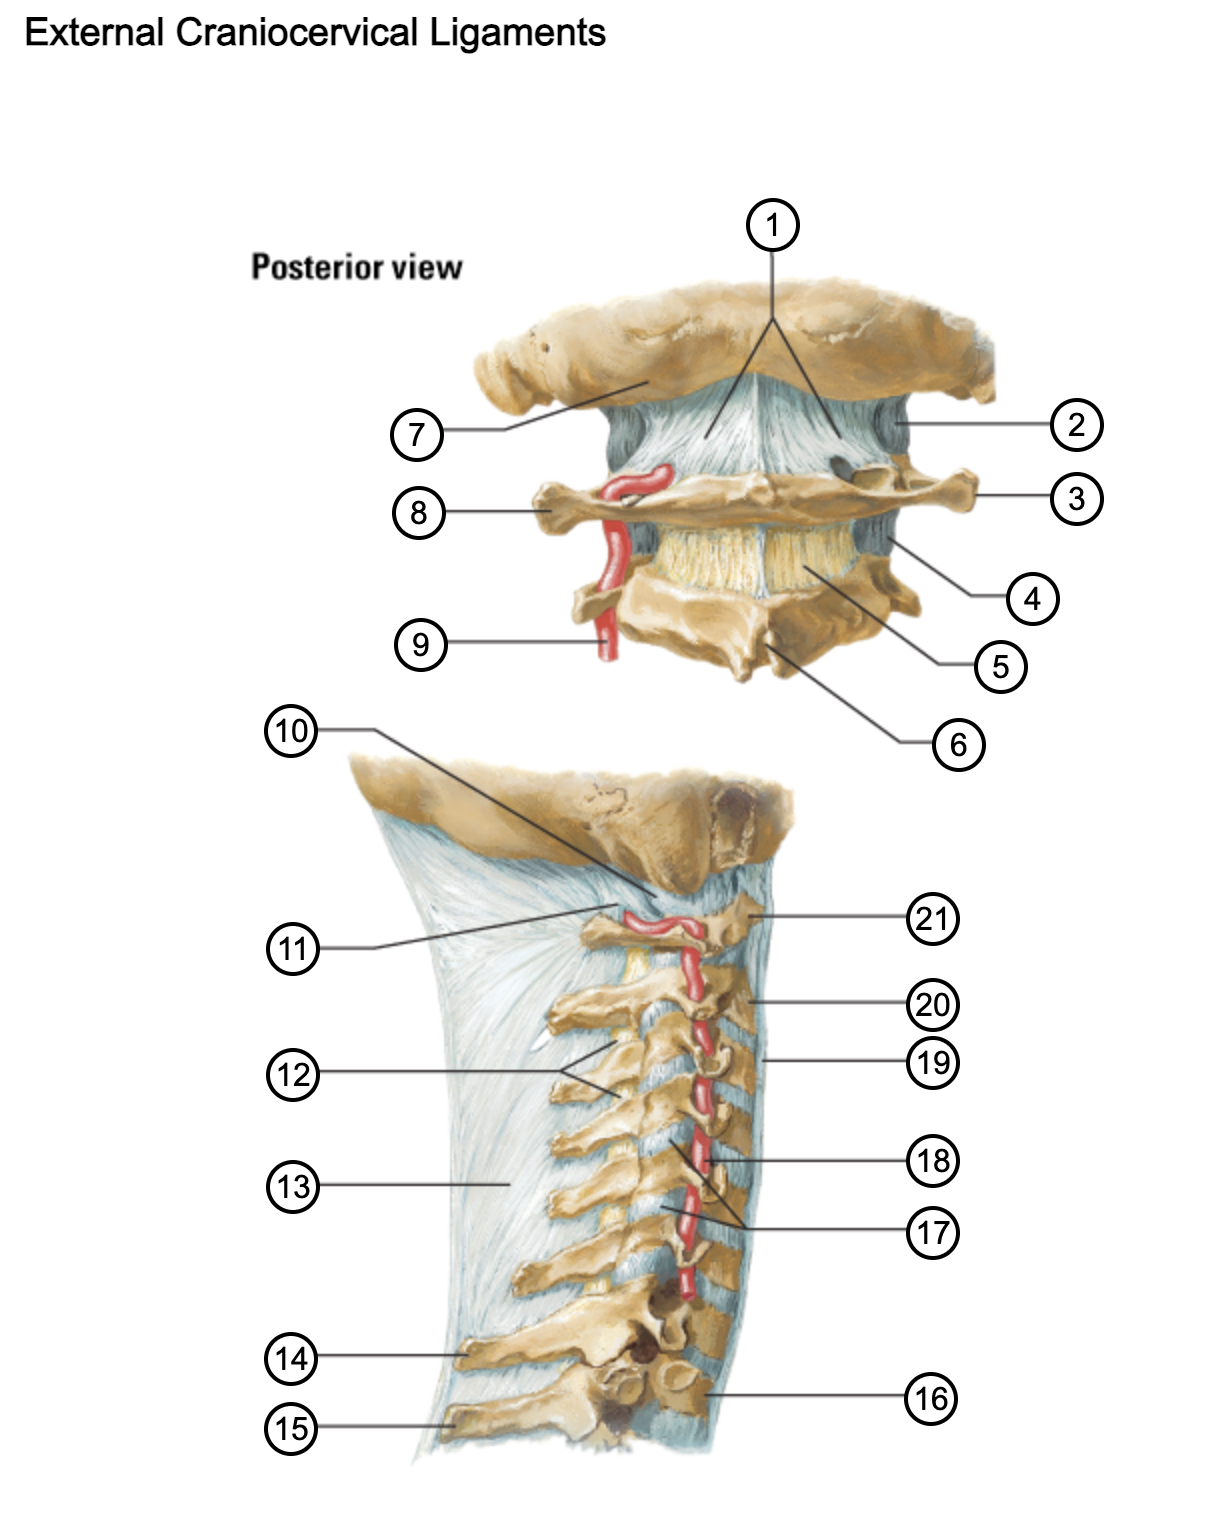

1

posterior antlantooccipital membrane

2

capsule of atlantooccipital joint

3

transverse process of atlas (C1)

4

capsule of lateral atlantoaxial joint

5

ligamenta flava

6

spinous process

7

occipital bone

8

transverse process of atlas (C1)

9

vertebral artery

10

capsule of atlantooccipital membrane

11

posterior atlantooccipital membrane

12

ligamenta flava

13

nuchal ligament

14

spinous process of C7 vertebra

15

spinous process of T1 vertebra

16

T1 vertebra

17

zygapophysical joints (C4-5 and C5-6)

18

vertebral artery

19

anterior longitudinal ligament

20

body of axis

21

Atlas (C1)